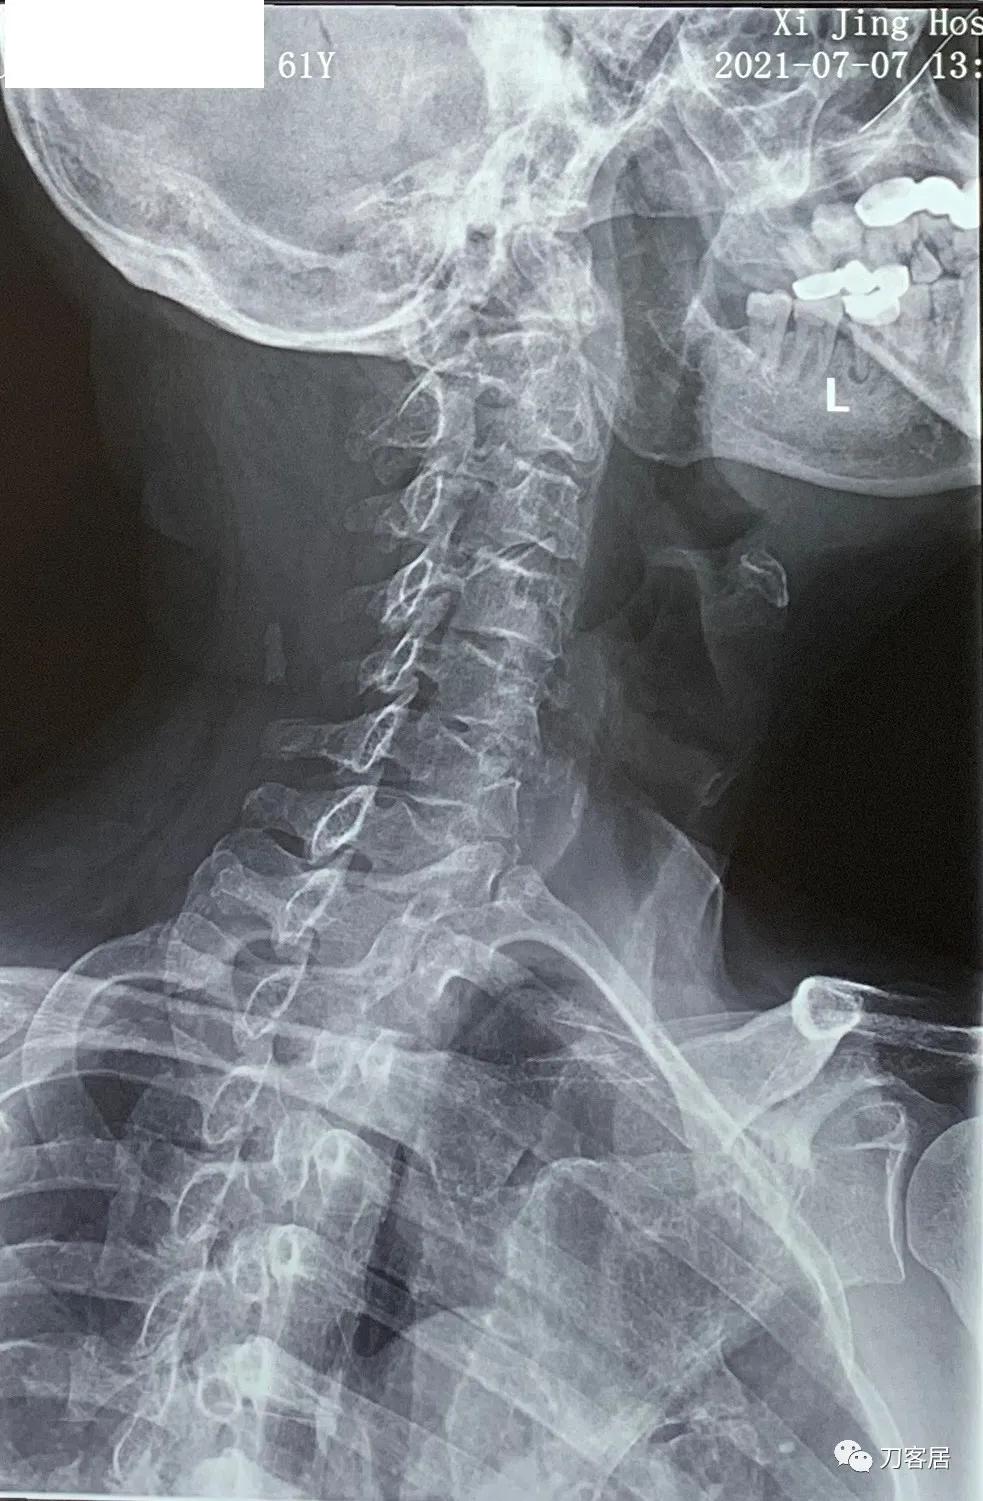

图11. 20210721颈椎过左斜位X线片,提示颈4-5椎间孔狭窄。